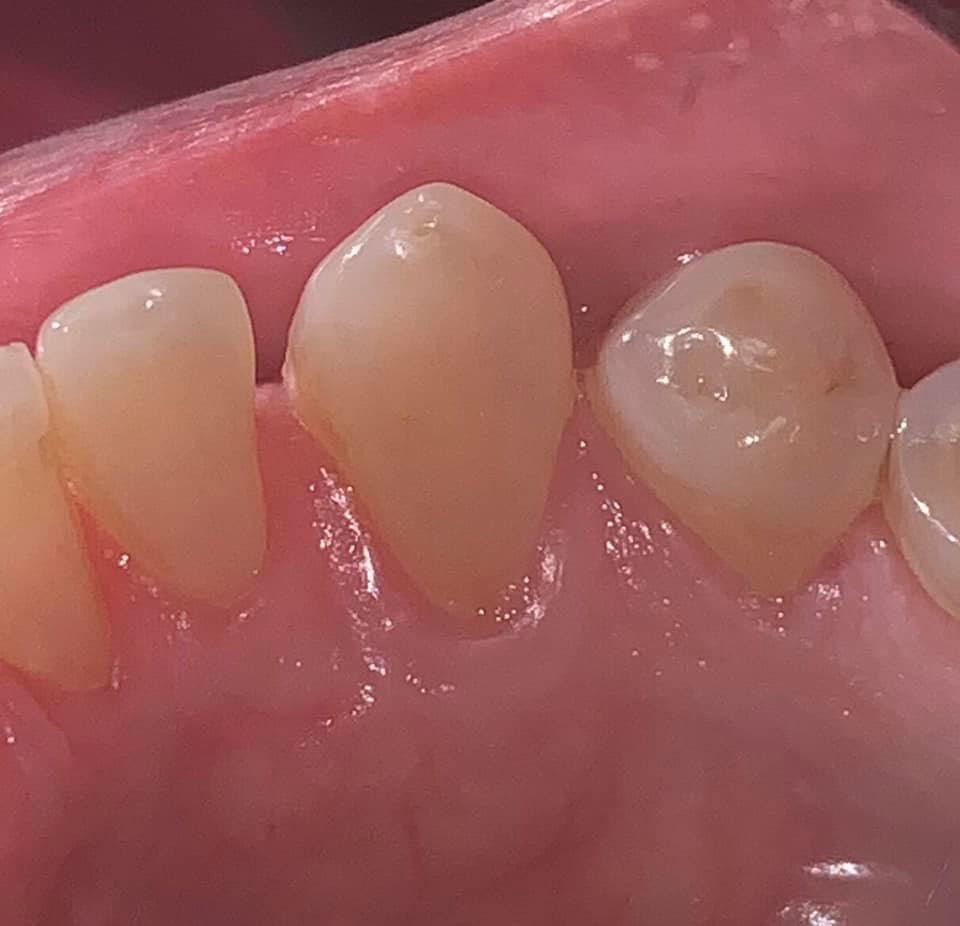

BEFORE AND AFTER PICTURES: